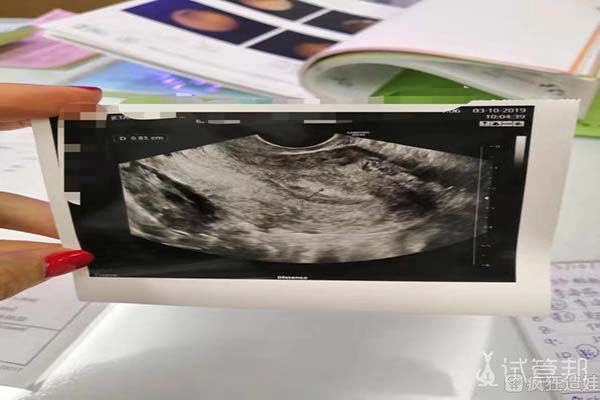

在移植的时候,我当时选择的是移植囊胚,也就是在受精卵培育到第5-6天的时候,进行的移植的时候,检查的时候子宫内膜的厚度不是很好,所以当月并没有进行移植。之后我开始用药,在第二个月终于子宫内膜厚度达标了,开始进行移植。很幸运的在移植后的14天进行检查的时候,就检查出了成功怀孕。

最后成功获取了23颗卵子,并配成了15颗受精卵。经过了5、6天的培养后,进行了基因筛查,有6颗是女胚胎。移植过程很简单,也很快。移植结束后我在医院休息了两个多小时,就回了宾馆。在宾馆呆了三天,才回国。